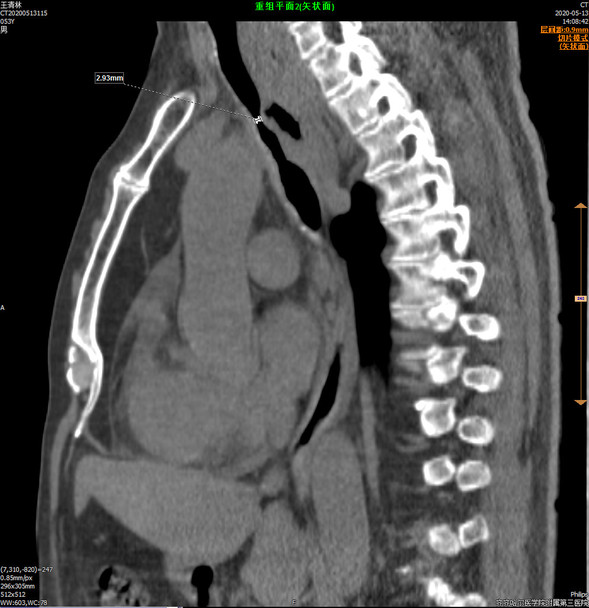

手术前的CT影像图

术前气管狭窄段直径只有2毫米

王先生的呼吸困难之所以如此严重是因为肿瘤侵犯气道非常广泛,从气管中上段一直延续到左主支气管,气管的最窄直径只有2毫米,而如此严重的狭窄又导致大量的痰液潴留及反复的肺感染。另外,毗邻食管的气管壁尤为菲薄,随时可能破溃导致气管食管瘘,增加窒息风险。下一步为彻底解决气道梗阻,最佳的方案就是气管支架植入。